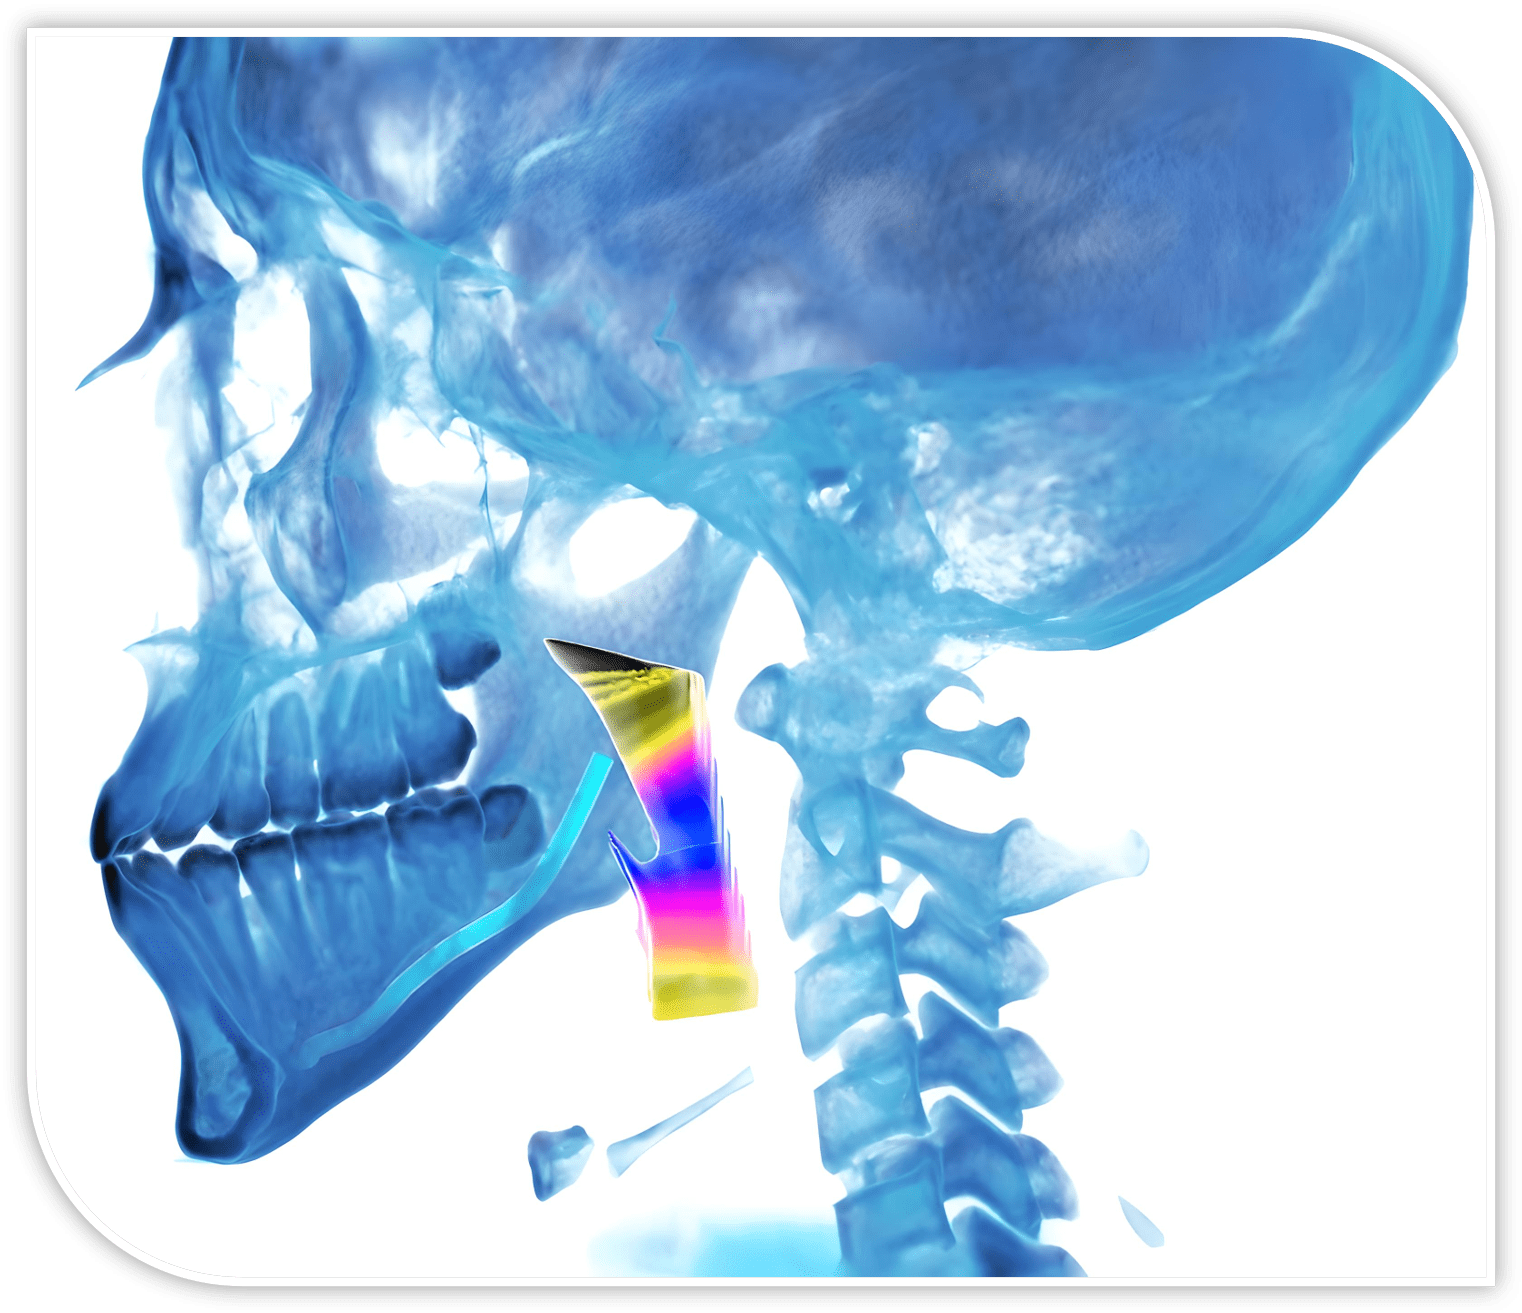

Dental Imaging Diagnostics

Custom CBCT interpretations, surgical guides, consultation, and CE — all delivered by Oral & Maxillofacial Radiologists, tailored for today’s dental practice.